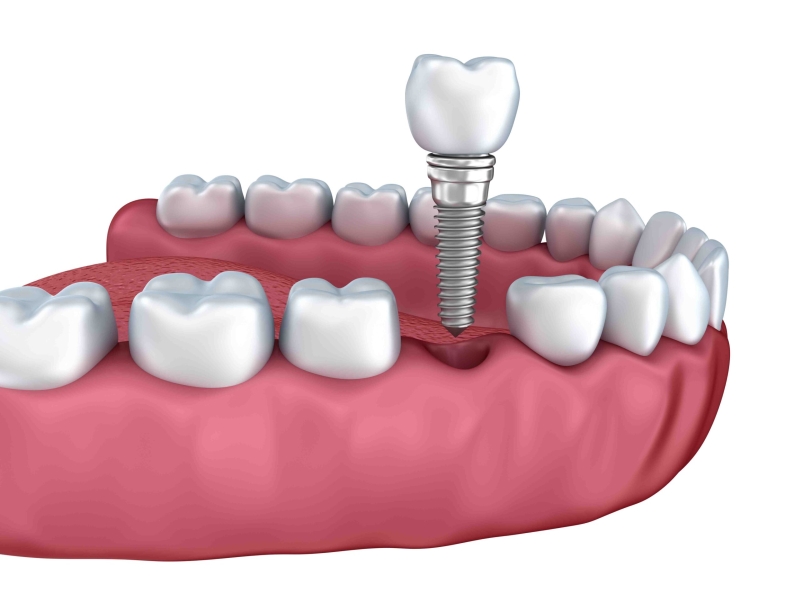

همانطور که گفتیم عوامل مختلفثی بر قیمت ایمپلنت دندان تاثیر می گذارند. وقتی به دندان پزشک متخصص مراجعه کنید، همه این موارد را برای شما توضیح خواهد داد. پیش از آن که به توضیحات جزئی بپردازیم، گفتن این نکته حائز اهمیت است که منظور از ایمپلنت در این متن همان پایه و پیچ هایی هستند که برای انجام عمل ایمپلنت دندان مورد استفاده قرار می گیرند. به این پایه و پیچ ها اصطلاحا فیکسچر هم می گویند. در ادامه به صورتی جزئی به بررسی این موارد می پردازیم.

قدرت فک و لثه از جمله مواردی هستند که در تعداد ایمپلنت ها تاثیر می گذارد. عامل مهم دیگر کنار هم بودن یا نبودن جای خالی دندان هاست. اگر 5 جای خالی دندان در نقاط مختلف دهان باشند، برای آن ها 5 ایمپلنت نیاز است در حالی که اگر تعدادی از همین دندان ها نزدیک به هم باشند این عدد می تواند به 3 کاهش پیدا کند. اگر جای خالی دندان در فک بالایی باشد ایمپلنت های بیشتری مورد استفاده قرار می گیرد، چرا که فک بالا استخوان ضعیف تری دارد. کسانی که دندان قروچه دارند یا دارای عضلات مفصلی در فک هستند نیز، ایمپلنت های بیشتری نیاز خواهند داشت. نظر دقیق در این مورد را دندان پزشک پس از معاینه شما ارائه می کند. داشتن استخوان های بیشتر و متراکم تر باعث می شود ایمپلنت کمتری نیاز داشته باشید. متحرک یا ثابت بودن دندان ها نیز موضوعی است که بر تعداد ایمپلنت ها تاثیر می گذارد. دندان های متحرک تعداد ایمپلنت کمتری نسبت به دندان های ثابت نیاز دارند.

درباره روکش هم باید گفت، تعداد روکش ها دقیقا همان تعداد تعداد دندان هایی است که می خواهید ایمپلنت کنید. مثلا اگر چهار جای خالی دندان دارید حتی اگر کنار یکدیگر هم باشند به 4 روکش یا تاج دندان نیاز دارید.